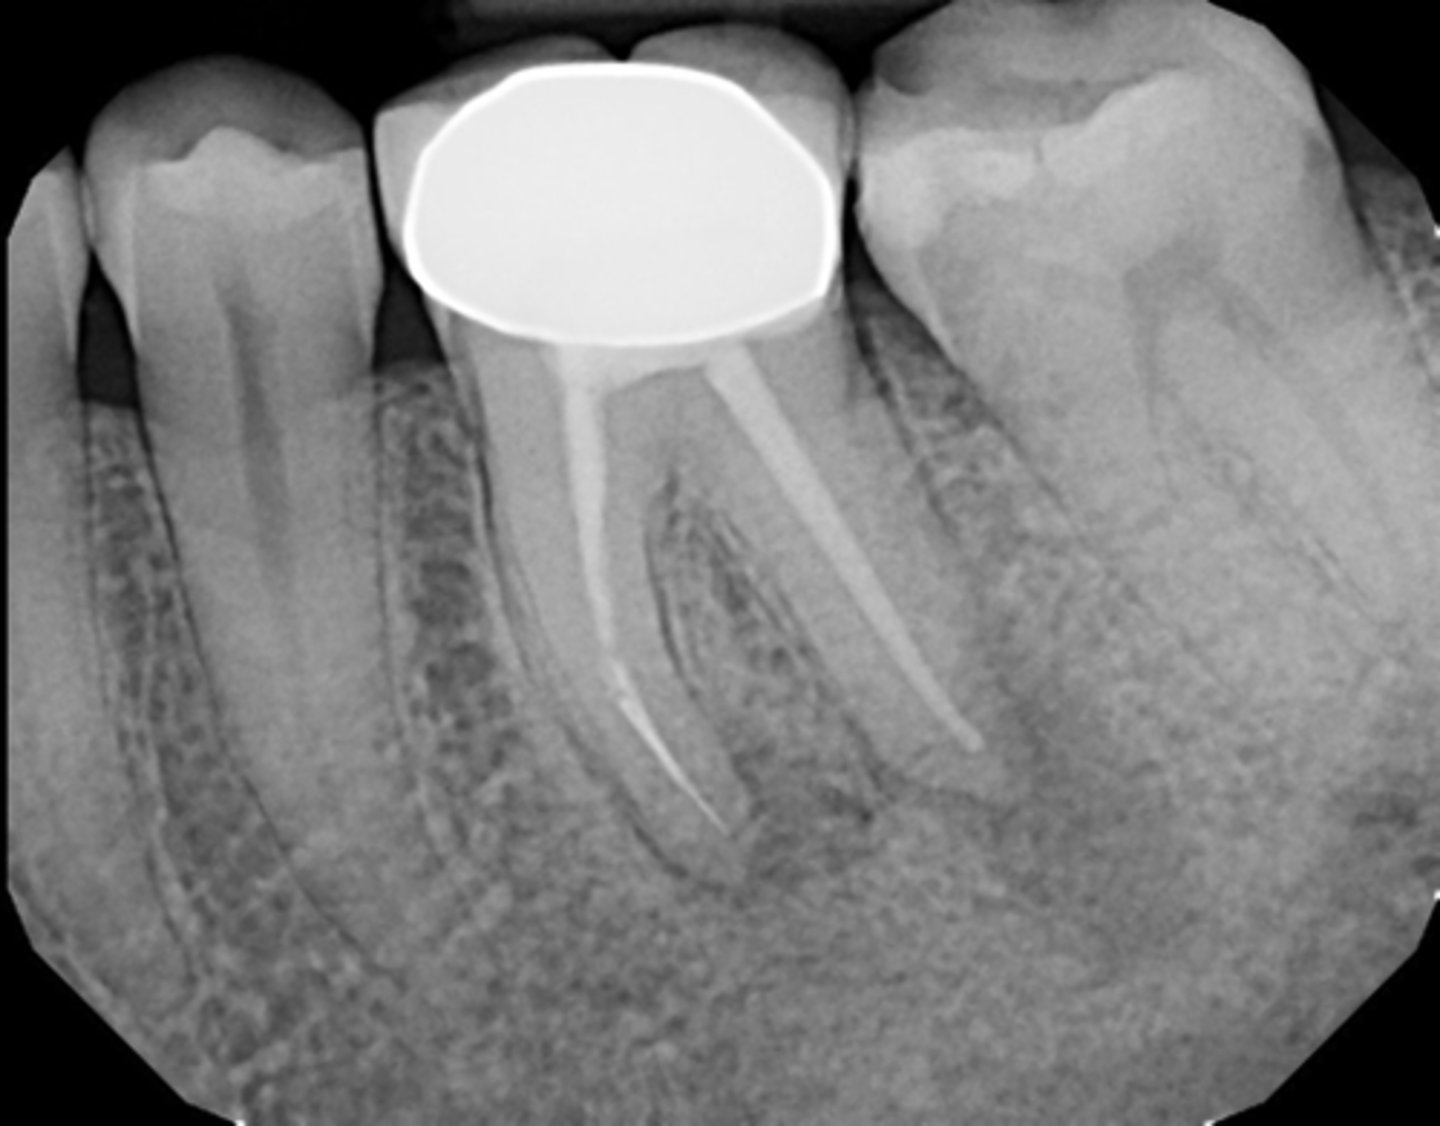

calcified/non-negotiable canal

What is the cause of this apical radiolucency?